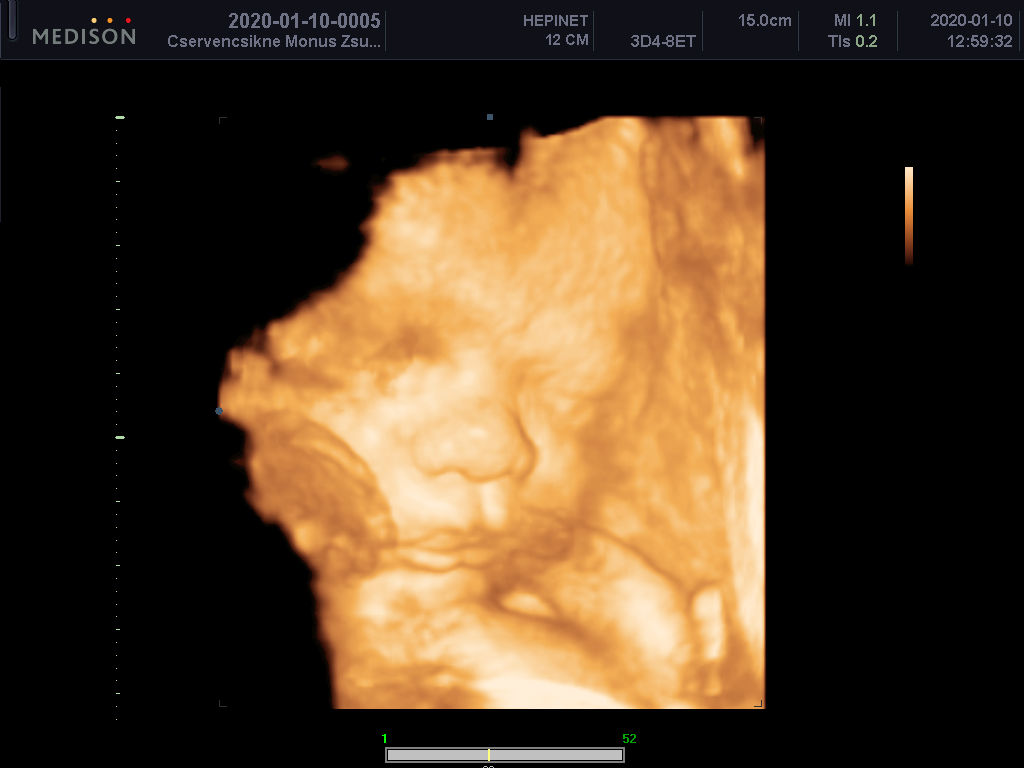

33. heti 4D ultrahang 2020.01.10.2020.02.08. by sanyiFinom formák csöpki száj.Állítólag kicsit le vagyunk maradva.